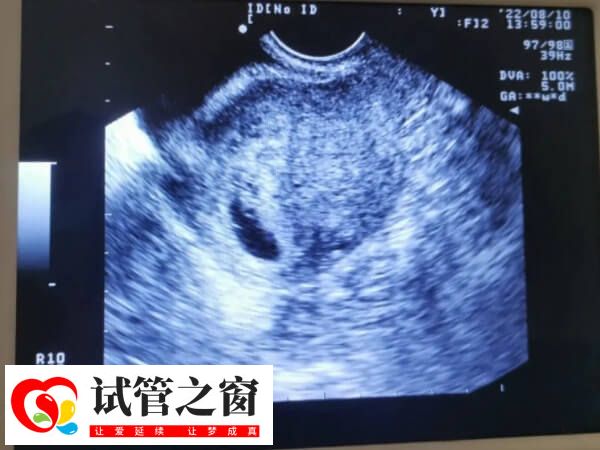

胎芽是妊娠早期形成的组织,是早孕时胚胎发育时期的一个必经的阶段,通常情况下,试管二超的时候胎芽在1.3-1.7厘米才是比较合适的,此情况下说明胚胎发育是非常良好的,而不足1.3cm的胎芽就偏小了,但是此情况下,若是女性hcg激素翻倍情况正常,而且B超检查的孕囊大小等数值与陪她是符合的,那么试管二超胎芽不足1.3厘米就是正常的。

当然若是试管二超胎芽不足1.3厘米,而女性hcg激素翻倍情况不正常,即没有达到隔天翻倍,或者是B超检查到的孕囊大小等数值与胎芽大小不足1.3厘米不太符合的话,那么就是不正常的,此情况下可能与胚胎质量差、激素水平低等因素有一定的关系,患者需配合医生做进一步检查与治疗,以使其尽快恢复正常,必要情况下需终止妊娠。